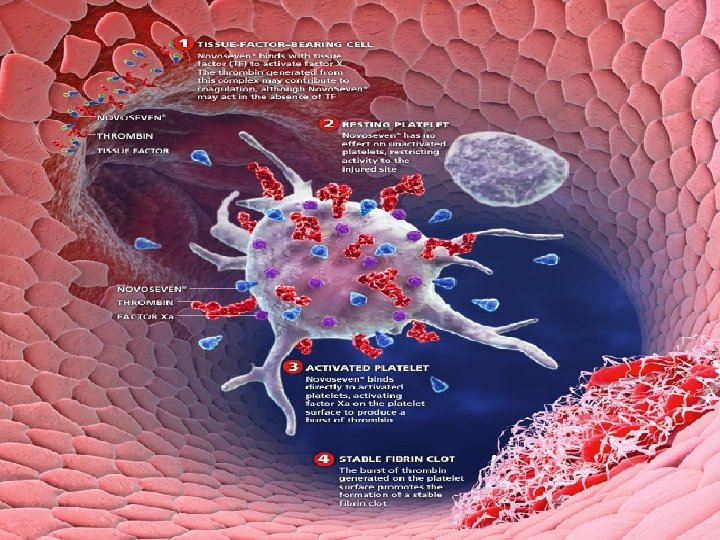

Ингибиторные формы гемофилий А и В! n n Лечение Очень большие дозы ф. VIII и ф. IX Реализовать обходной путь • Autoplex T – (NABI) • PPSB – (V, VIII, X) • Novoseven (VIIa) – (Novo Nordisk) • FEIBA VH (II, VII, IX, X) – (Baxter/Immuno) !

Novoseven (рекомбинантный фактор VIIа) n n Ампулы с лиофизированным порошком ф. VIIa, содержащие 1, 2 и 4, 8 мг вещества. 90 мкг/кг каждые 2 ч в/в струйно При тяжелых кровотечениях инъекции продолжать в течение 3 -6 часов после остановки кровотечения. Не вводить капельно!